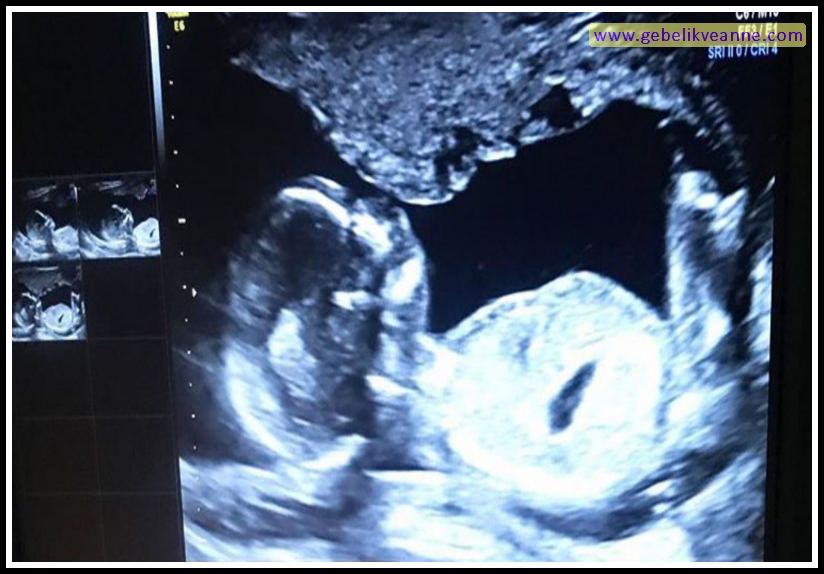

17 haftalık gebelik ultrason ile bebeğin kaş ve kirpikleri büyümeye adım attığı görülebilir. Hafta, anne adaylarının bulantı ve kusma gibi gebelik belirtilerini atlatarak daha sakin ve keyifli bir döneme geçiş yaptığı bir gebelik haftasıdır. 4 ay 2 günlük gebelik 17 hafta 4 günlük gebelik:

17 haftalık anne karnı görüntüleri; 17 haftalık bebek nasıl görünür? 17 hafta hamilelik kaç aylık oluyor?

17 haftalık anne karnı görüntüleri; Bebek aynı oranda gelişmiş olsa da bazı anne adaylarının cilt yapısı daha sıkı olduğundan henüz esneme başlamamış olabilir. 17 haftalık gebelik ultrason ile bebeğin kaş ve kirpikleri büyümeye adım attığı görülebilir.